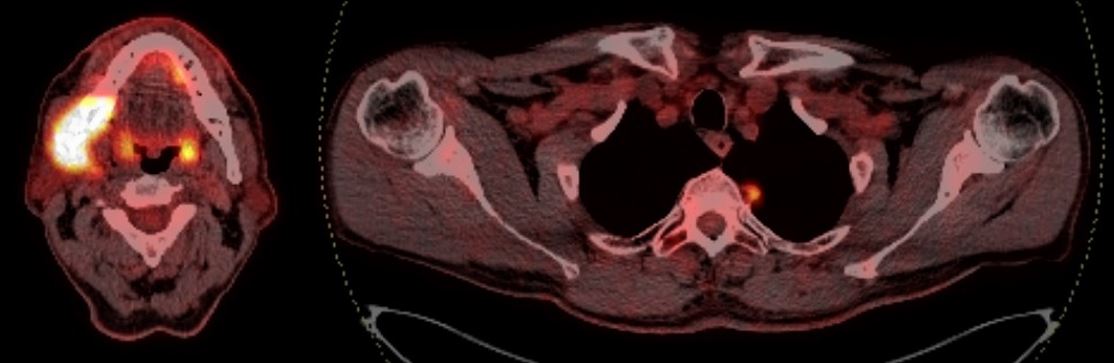

Описание случая. Представлен случай агрессивного течения низкодифференцированной крупноклеточной нейроэндокринной карциномы шейки матки у пациентки 40 лет. Отмечаются сложности и ошибки подходов к верификации диагноза, а также необходимость в применении расширенного диагностического комплекса для выбора оптимальной тактики ведения. Всего пациентке проводили IV линии ХТ после оперативного лечения и многоэтапного иммуногистохимического исследования. Однако несмотря на все предпринятые усилия, состояние пациентки резко ухудшилось, и она скончалась через 2 года и 1 мес от момента первичного обращения.

Заключение. Отсутствие специфических симптомов, агрессивность течения, сложность диагностики на всех этапах и ограниченные возможности методов лечения определяют необходимость создания и развития отдельных центров по лечению НЭО любой степени злокачественности и различной локализации.